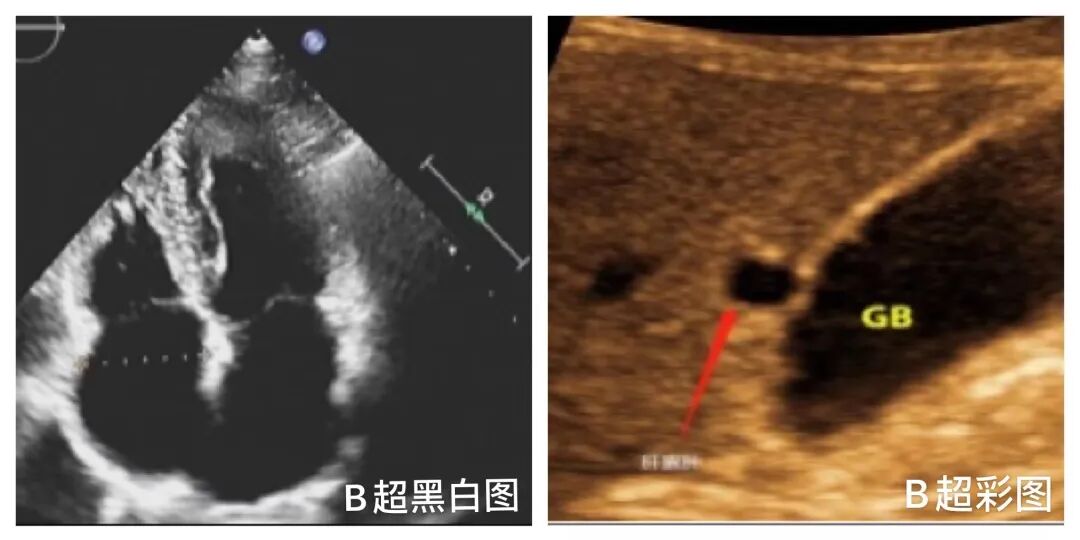

二、B型超声:即辉度调制型超声仪,全称为实时灰阶二维显像仪,二维超声图像如用伪彩色编码显示,称为B型彩色仪(B彩)。这也就是我们所说的B超。那么B超也不只是黑白图哦。他也有彩图,也就是我们常用的B彩(或伪彩),这种技术也对疾病非常有用,如在囊肿的判断上有着特殊的功能,观察效果极好。